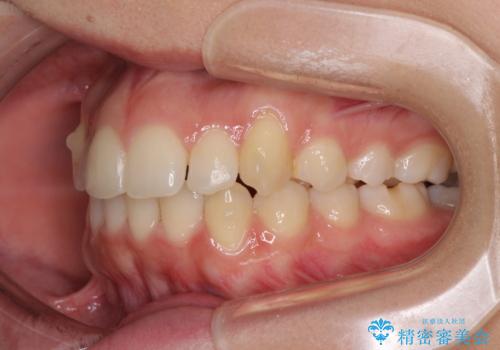

骨格的に左右にずれいている 前歯のデコボコをインビザラインで解消

- 前歯のデコボコと八重歯を気にして来院された患者様です。

叢生の程度は中等度であったため、IPR(歯と歯の間を削る)と歯列の側方拡大をメインに、インビザラインを用いて歯列を改善することとしました。

また、下顎骨の右側変位による右側臼歯の咬合を改善させるよう試みることとしました。

右側の咬合改善を目標に様々な手法を用いましたが、骨格的なズレによる不正咬合はインビザラインでは改善することができませんでした。